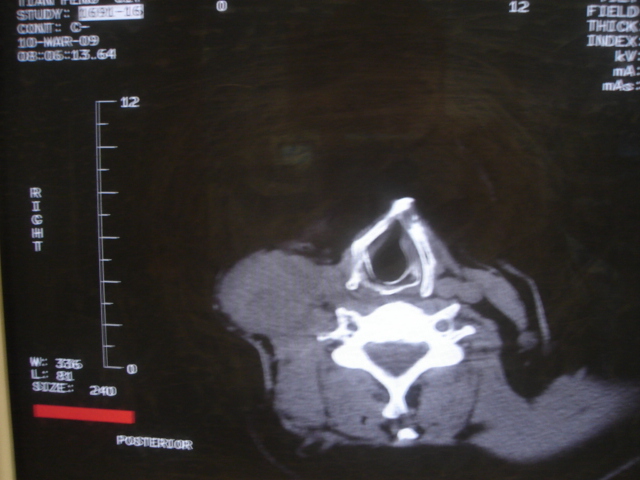

声门下区表面不光整,增厚呈局限性突起,未见局部浸润.

另声门区不规则突起,建议喉镜检查!

右侧颈部淋巴结转移,右声带乳头突起,乳头状瘤可能性大。

1)右侧颈部淋巴结转移瘤。2)右侧声带新生物,性质待定;建议喉镜检查(活检)。